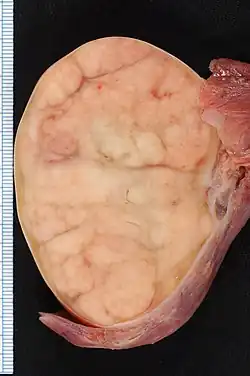

| 7.4 × 5.5-cm seminoma in a radical orchiectomy specimen. | |